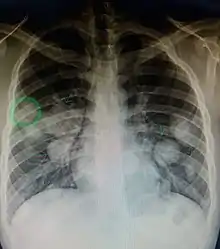

Initially, nearby lymph nodes are struck early.[9] The lungs, liver, brain, and bones are the most common metastasis locations from solid tumors.[9]

- Lung metastasis: cough, hemoptysis and dyspnea[9] (shortness of breath)